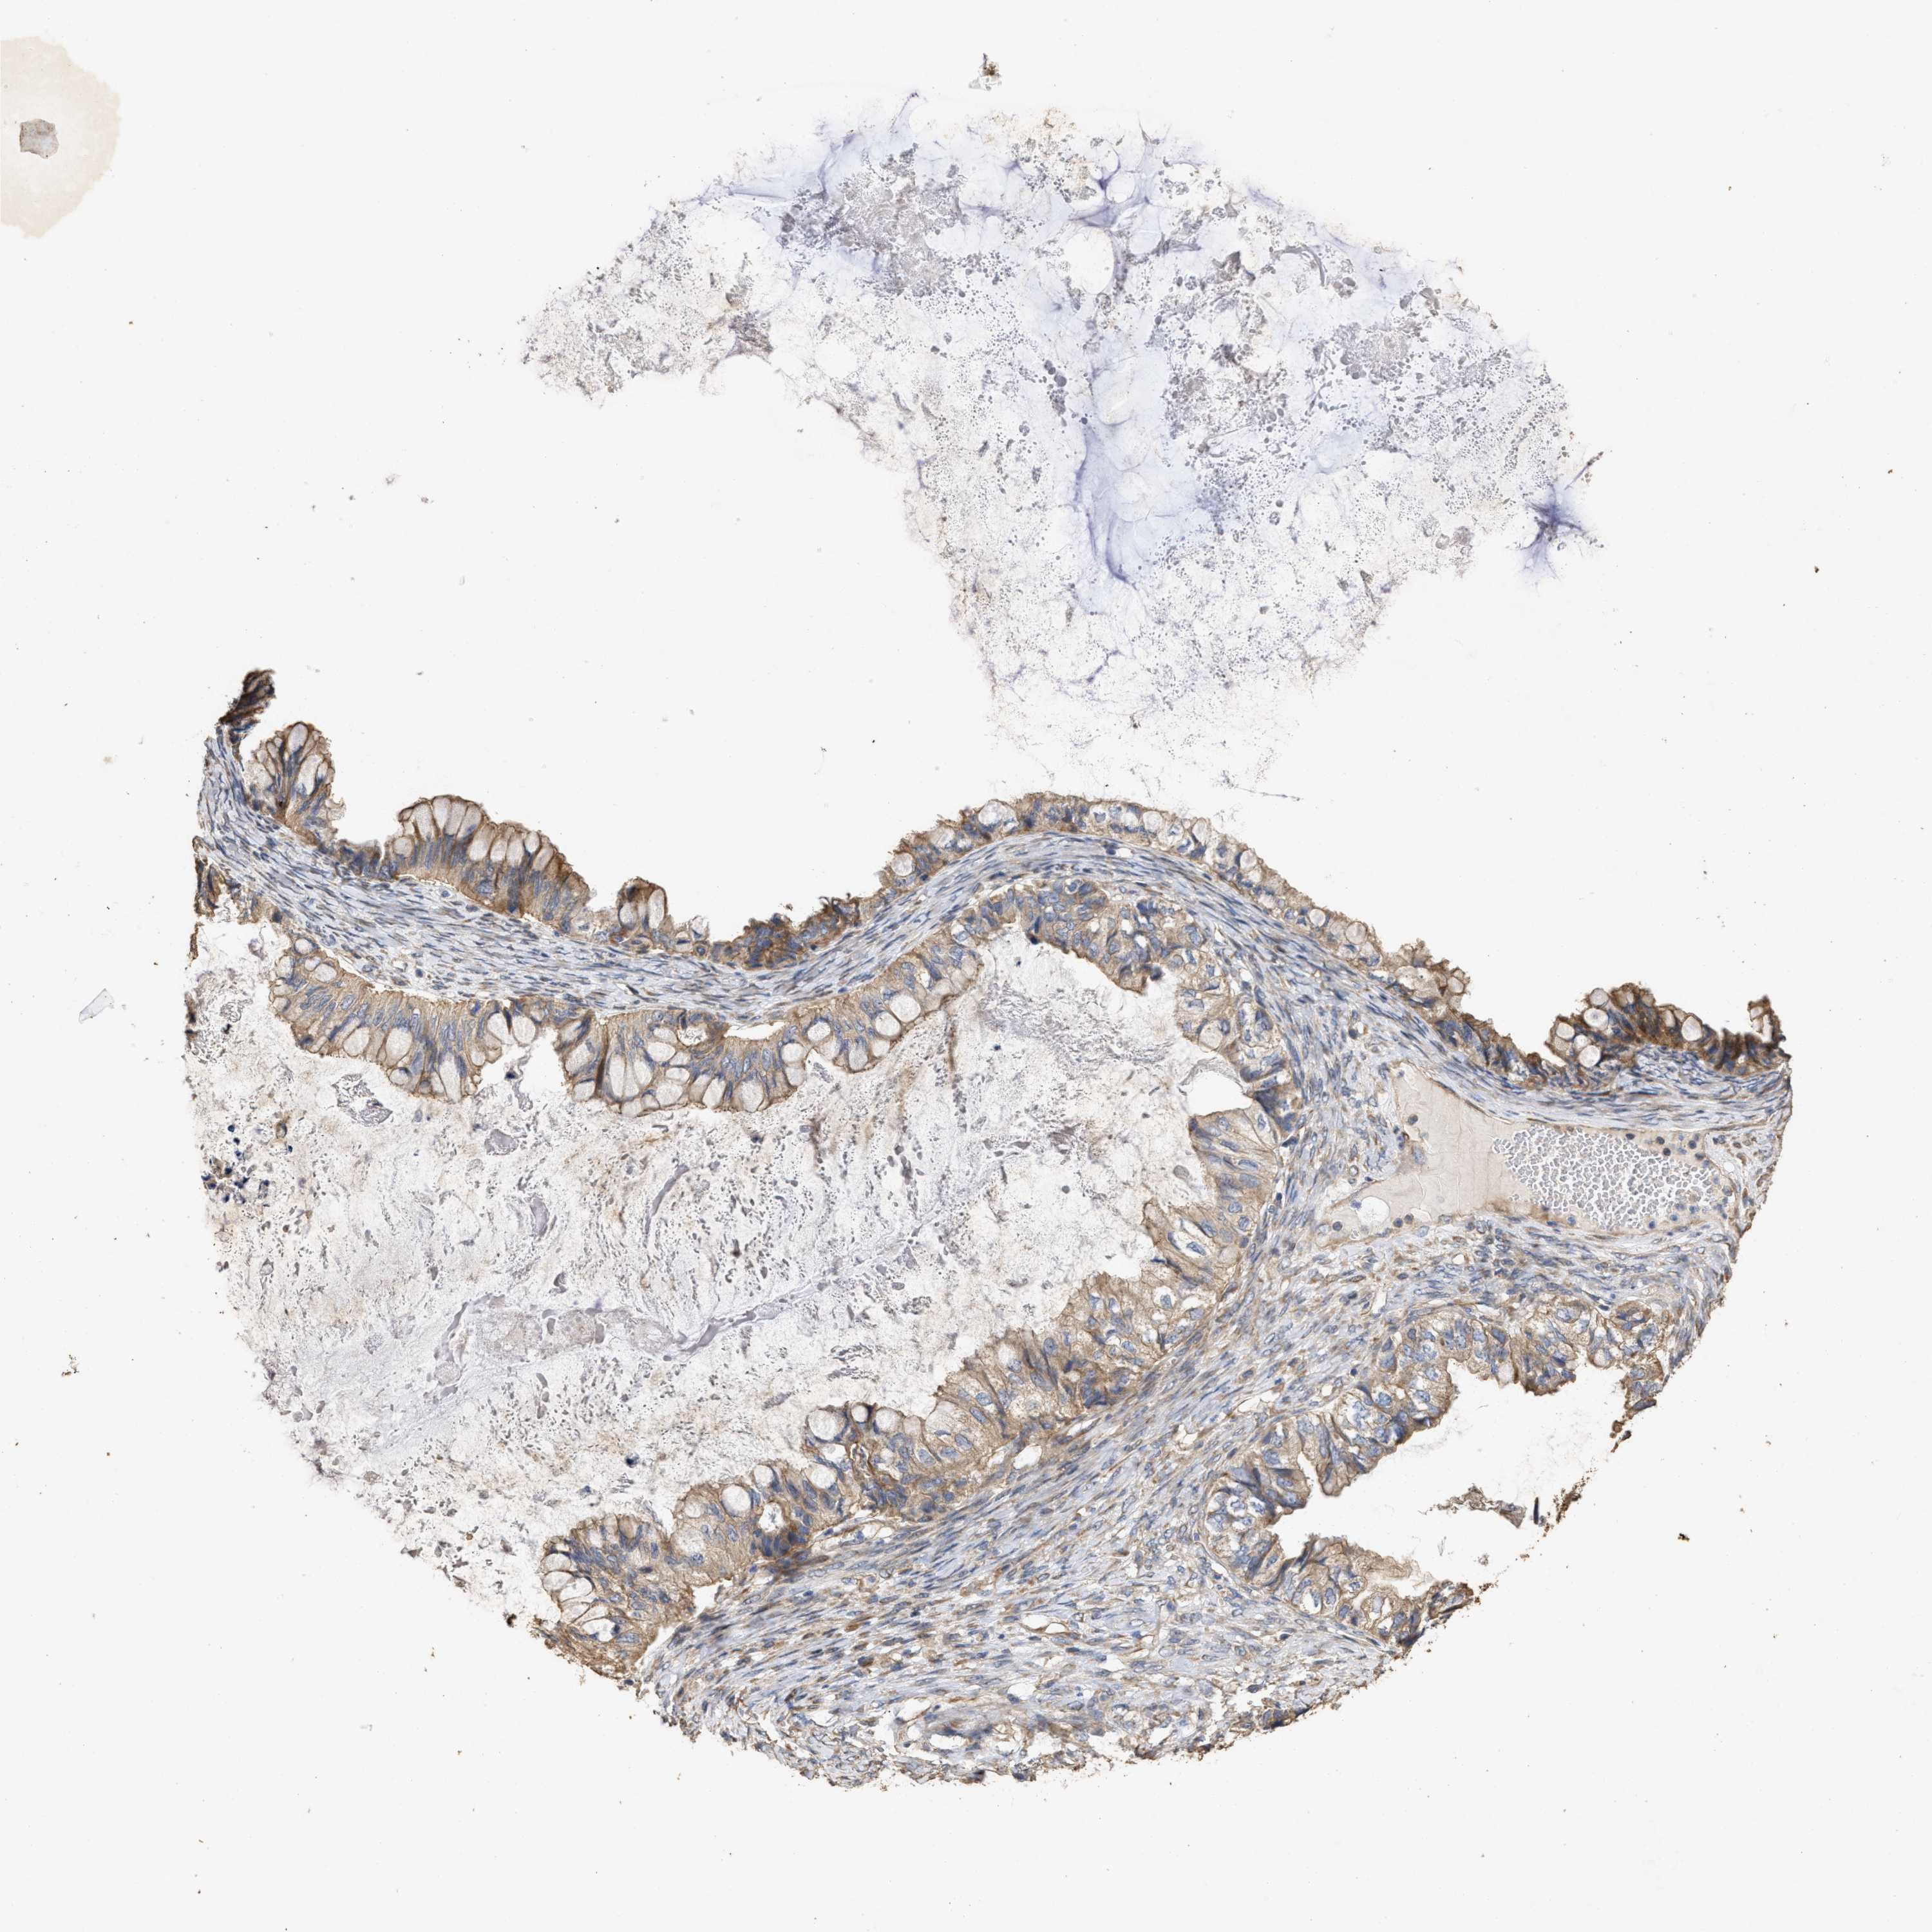

OVARIAN CANCER - Protein expressioni

A mouse-over function shows sample information and annotation data. Click on an image to view it in a full screen mode. Samples can be filtered based on level of antibody staining by selecting one or several of the following categories: high, medium, low and not detected. The assay and annotation is described here.

Note that samples used for immunohistochemistry by the Human Protein Atlas do not correspond to samples in the TCGA dataset.

Antibody stainingi

Antibody staining in the annotated cell types in the current human tissue is reported as not detected, low, medium, or high, based on conventional immunohistochemistry profiling in selected tissues. This score is based on the combination of the staining intensity and fraction of stained cells.

Each image is clickable and will lead to virtual microscopy that enables deeper exploration of all samples and also displays staining intensity scores, fraction scores and subcellular localization as well as patient and tissue information for each sample.

Antibody CAB012302

Cystadenocarcinoma, mucinous, NOS